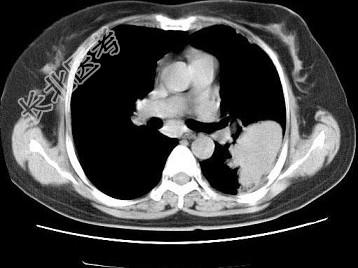

- 单项选择题女,52岁, 左侧背痛1月,胸部CT如图, 最可能的诊断为 ( )

A、左肺中央型肺癌

B、左肺周围型肺癌

C、左肺感染

D、左肺炎性假瘤

E、肺隔离征